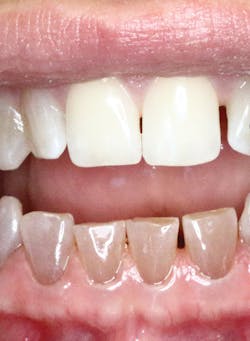

Clinical features—Discoloration (see Figure 2) is noticed more in the primary teeth than in the permanent teeth of those with osteogenesis imperfecta. The teeth have a brown, yellow to gray color. The teeth presented in this image are all natural teeth with the maxillary teeth appearing clinically normal and bright white. This is typical in OI; some teeth may appear normal in color.

Oral ramifications affect the dentin with color variations, and this is evident in the mandibular teeth (see Figure 3). There are significant oral manifestations that will vary in the effects on the teeth, the pulp, and the overall oral clinical presentation of the patient.

Treatment—Reconstruction of the teeth is often needed for patients who have extensive destruction. The images presented in this article show that clinically the maxillary teeth are esthetically pleasing and even bright white. The mandibular teeth do exhibit the typical brown opalescent teeth that are seen with this type of OI.